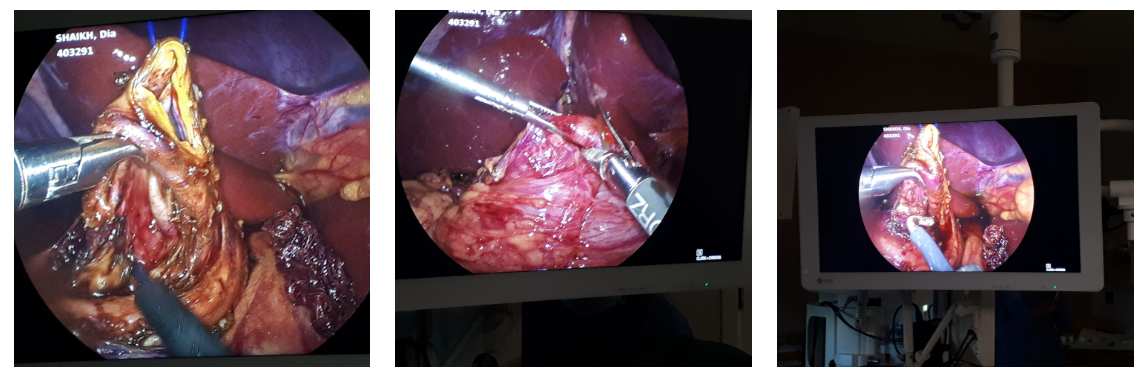

Successful Laparoscopic Excision of Type 1c Choledochal Cyst

13-year-old girl successfully treated by total laparoscopic excision of type 1-C choledochal cyst and hepatico-duodenostomy. She presented with recurrent abdominal pain, post feeding discomfort, nausea, occasional fever and vomiting.